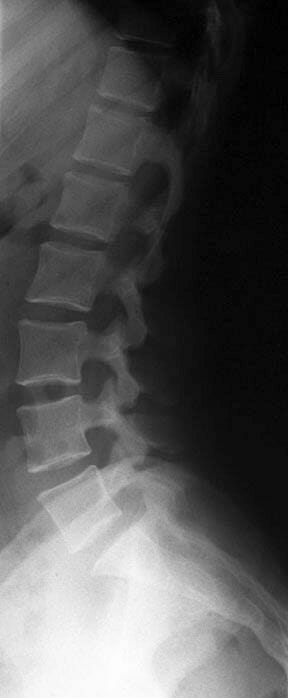

X-ray กระดูกสันหลัง

การตรวจ X-ray คงเป็นอะไรที่คุ้นหูทุกคนกันอยู่แล้วนะครับ เพราะเป็นวิธีมาตรฐานที่หมอเกือบทุกแผนกมักจะส่งตรวจกัน

โดยทั่วไปการตรวจ X-ray ของหมอกระดูกสันหลังมีจุดประสงค์เพื่อดูแนวกระดูกนั่นเองครับ โดยในความเป็นจริงแล้วในภาพถ่าย X-ray หนึ่งภาพ สามารถที่จะให้ข้อมูลเราได้มากมายไม่ว่าจะเป็น การเรียงตัวของกระดูก, การแตกหักหรือการยุบตัวของกระดูก, การเสื่อมของหมอนรองกระดูก และความเสียหายของกระดูกที่เกิดจากการติดเชื้อหรือเนื้องอก

อย่างไรก็ตามการตรวจ X-ray ก็มีข้อควรระวังอยู่บ้าง เพราะรังสี X-ray เป็นรังสีที่อาจมีอันตรายต่อร่างกายได้ ถ้าได้รับรังสีไปในปริมาณที่เยอะเกินไป และการตรวจด้วยรังสี X-ray มักจะไม่ทำในผู้ป่วยหญิงที่ตั้งครรภ์เพราะอาจส่งผลกระทบต่อเด็กในท้องได้ (อย่างไรก็ตามในกรณีที่จำเป็นต้องทำ X-ray จริงๆเช่นผู้ป่วยได้รับอุบัติเหตุมีกระดูกหักรุนแรง ก็อาจจำเป็นต้องพิจารณาทำเป็นกรณีๆไป)

ข้อดีของการทำ X-ray ก็คือความเร็วครับ เพราะใช้เวลาทำสั้นมากเพียงเดินเข้าไปในเครื่องและรอเจ้าหน้าที่กดถ่ายภาพ ใช้เวลาไม่ถึง 1 นาทีต่อภาพเท่านั้นเอง

ในส่วนของข้อจำกัดของ X-ray นั้นคือเราจะไม่สามารถบอกเห็นภาพหมอนรองกระดูกและเส้นประสาทได้ เพราะรังสี X-ray จะยิงทะลุผ่านอวัยวะเหล่านี้และทำให้เห็นเป็นเพียงช่องว่างเปล่าๆในภาพ X-ray ครับ